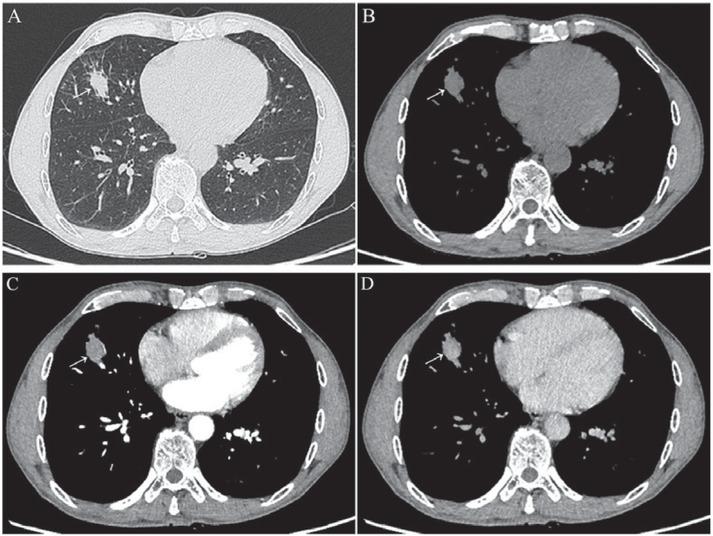

Figure 1